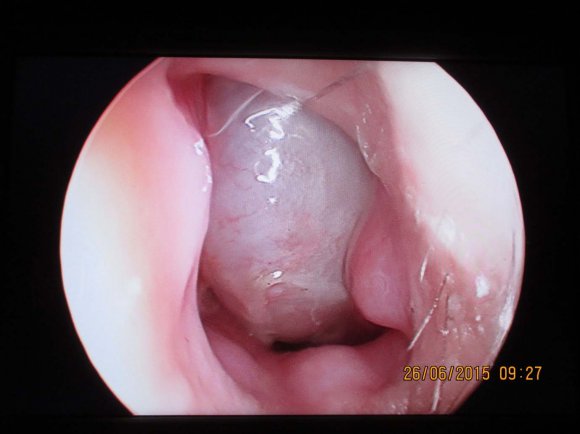

On anterior rhinoscopy, a non-tendergreyishwhite mass with smooth surface and soft consistency was seen in left side of nasal cavity. There was no nasal discharge or sinus tenderness.Diagnostic nasal endoscopy showed its attachment to the anteroinferior portion of septum partially obstructing the left nasal passage. Also there was mild DNS to right. (Figure 1) Endonasal endoscopic excision of the lesion was planned under general anaesthesia. The nasal mass was completely resected with a rim ofnormal septal mucoperiosteum and perichondrium under GA.There was no needfor any perioperative blood transfusion.The surgical specimen was sent for histopathological examination. (Figure 3) On gross examination, mass was whitish with smooth surface measuring 2x1.2 cm in size. On histopathological examination, section shows a lesion composed proliferating capillaries of various size lined by flattened endothelium lying in a fibrous stroma suggestive of lobular capillary haemangioma. There was no evidence of malignancy. (Figure 4) The patient has been followed up for a period of one year, and there is no recurrence of growth.